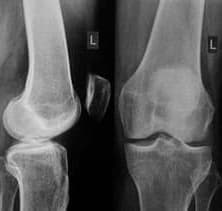

Η παρακάτω ακτινογραφία δείχνει την αναγέννηση της άρθρωσης του γόνατος:

Χάρη στην κρέμα Steplex, μπορείτε να θεραπεύσετε τις ασθένειές σας στο σπίτι σε ένα ή δύο μήνες. Το "Steplex" δεν δροσίζει και δεν αναισθητοποιεί, αλλά "ξανεκκινεί" το σώμα σε κυτταρικό επίπεδο, εξαλείφει την ίδια την αιτία του πόνου και βοηθά στην αποκατάσταση της υγείας των αρθρώσεων.